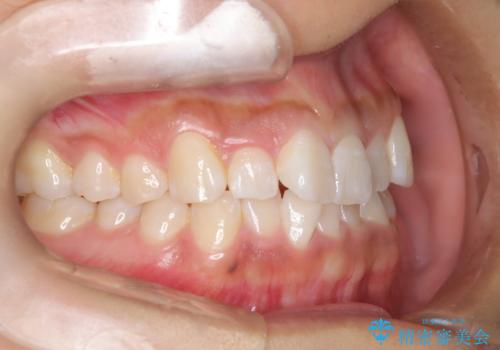

ワイヤー矯正で確実にガタつきを治したい セラミックブラケットによる治療

- 治療計画

- 前歯の叢生(がたつき)を主訴に来院された患者様です。以前マウスピース矯正をされていたそうでしたが、自身での継続が難しいことなどを理由に、ワイヤー矯正にて改めて矯正治療を希望されました。非抜歯にて治療を計画し治療を行いました。

歯の動きが良く、スムーズに治療を終了しました。一般的にワイヤー矯正はブラッシングが難しいのですが、毎回一生懸命セルフケアをされていたのが印象的です。治療においては、歯の衛生状態も一緒にチェック致します。